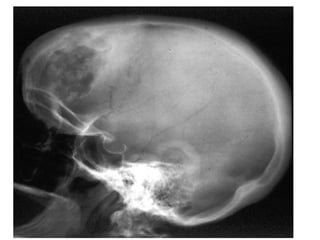

Acromegaly

• Acromegaly is a serious condition that occurs

when the body produces too much of the

hormones that control growth. ・ The hormone

most often affected is called growth hormone, or

GH. It ハ is produced by the pituitary gland, a tiny

organ at the base of the brain. ・・ Growth

hormone ハ promotes growth of bone, cartilage,

muscle, organs, and other tissues. ・・ When

there is too much growth hormone in the body,

these tissues grow larger than normal. This

excessive growth can cause serious disease and

even premature death.

Acromegaly • Acromegaly isa serious condition that occurs when the body produces too much of the hormones that control growth. ・ The hormone most often affected is called growth hormone, or GH. It ハ is produced by the pituitary gland, a tiny organ at the base of the brain. ・・ Growth hormone ハ promotes growth of bone, cartilage, muscle, organs, and other tissues. ・・ When there is too much growth hormone in the body, these tissues grow larger than normal. This excessive growth can cause serious disease and even premature death.